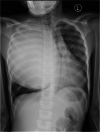

Case presentation: We present two patients from pastoralist (Maasai) communities in rural Tanzania with long-standing chest pain accompanied by hemoptysis. Both were managed surgically after diagnosis, but one patient died of the complications following rapture of the cyst during surgery. Histopathological evaluation of the specimens confirmed the diagnosis of giant hydatid cysts.